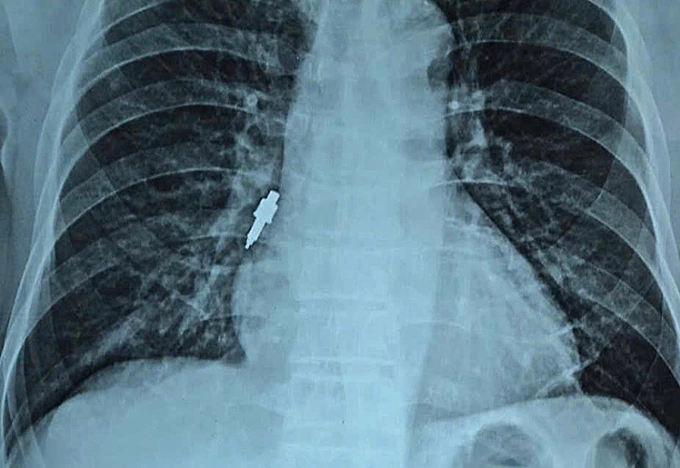

Dị vật kim loại nằm sâu trong đường thở. Ảnh: Bệnh viện cung cấp

Ngày 26/11,đại diện viện cho biết nội soi gắp thành công dị vật nằm sâu trong phế quản phải của bệnh nhân. Dị vật là một dụng cụ nha khoa bằng inox,trơn nhẵn,dài 2,5 cm và có đường kính lớn nhất lên tới 1 cm.